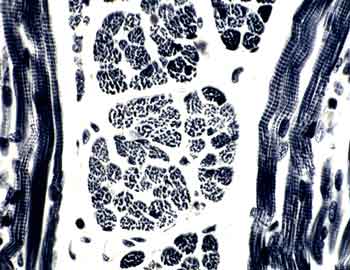

Visión general: se trata de una tinción inmunohistoquímica para detectar filamentos gliofibrilares de los astrositos (Proteína gliofibrilar ácida). Se distingue la matriz fibrilar de la membrana pioglial intensamente teñida de marrón en la superficie de la corteza cerebral así como el citoesqueleto de los astrocitos.

Visión específica: el conglomerado fibrilar de la membrana pioglial perteneciente a los gliofilamentos de las prolongaciones astrocitarias dirigidas a la superficie cerebral así como los filamentos que ocupan los somas de la astroglia fibrilar y protoplásmica presentan un intenso inmunomarcaje.